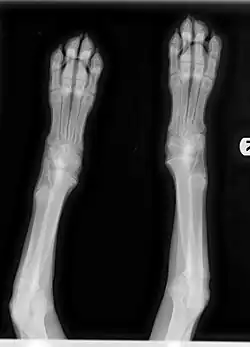

Radiographic features

Diagnosis relies on clinical signs and characteristic changes in radiographic images of the metaphyses. Bone changes can be observed on radiograph, and the disorder may progress to actual angular limb deformity. In the early stage of the illness, the metaphyseal area on X-ray may be observed to have an uneven radiolucent zone parallel to the physis with a thin band of increased radiodensity directly bordering the physis. Early stage radiographic changes have sometimes been described as having a "moth-eaten" appearance (see Figure 3). As the disease progresses, the radiolucent line may disappear and radiodensity may increase in the affected area as the body attempts to repair damage. Relapses can cause new radiolucent lines. This area is often followed by a dark line at the metaphysis, which may progress to new bone growth on the outside of that area. This area represents microfractures in the metaphysis and bone proliferation to bridge the defect in the periosteum.[7]